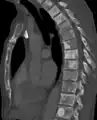

- Sclerosis of the bones of the thoracic spine due to prostate cancer metastases (CT image)